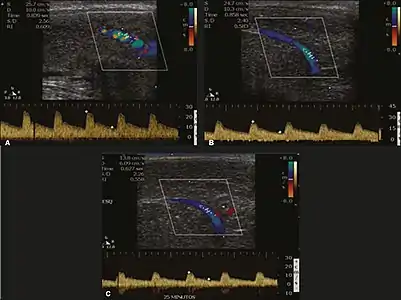

Erection can be induced by injecting 10–20 µg of prostaglandin E1, with evaluations of the arterial flow every five minutes for 25–30 min (see image). The use of prostaglandin E1 is contraindicated in patients with predisposition to priapism (e.g., those with sickle cell anemia), anatomical deformity of the penis, or penile implants. Phentolamine (2 mg) is often added. Visual and tactile stimulation produces better results. Some authors recommend the use of sildenafil by mouth to replace the injectable drugs in cases of contraindications, although the efficacy of such medication is controversial.[45]

Before the injection of the chosen drug, the flow pattern is monophasic, with low systolic velocities and an absence of diastolic flow. After injection, systolic and diastolic peak velocities should increase, decreasing progressively with vein occlusion and becoming negative when the penis becomes rigid (see image below). The reference values vary across studies, ranging from > 25 cm/s to > 35 cm/s. Values above 35 cm/s indicate the absence of arterial disease, values below 25 cm/s indicate arterial insufficiency, and values of 25–35 cm/s are indeterminate because they are less specific (see image below). The data obtained should be correlated with the degree of erection observed. If the peak systolic velocities are normal, the final diastolic velocities should be evaluated, those above 5 cm/s being associated with venogenic ED.[45]

Graphs representing the color Doppler spectrum of the flow pattern of the cavernous arteries during the erection phases. A: Single-phase flow with minimal or absent diastole when the penis is flaccid. B: Increased systolic flow and reverse diastole 25 min after injection of prostaglandin.[45]

Longitudinal, ventral ultrasound of the penis, with pulsed mode and color Doppler. Flow of the cavernous arteries at 5, 15, and 25 min after prostaglandin injection (A, B, and C, respectively). The cavernous artery flow remains below the expected levels (at least 25–35 cm/s), which indicates ED due to arterial insufficiency.[45]